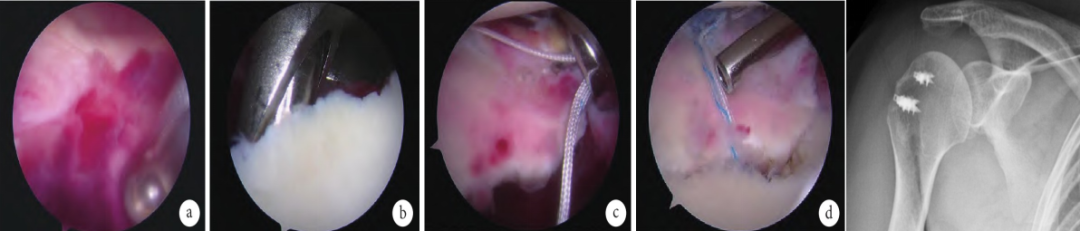

关节镜是诊断肩袖损伤的最准确的方法,也是治疗肩袖损伤的一种方式,以往认为适用于中小型肩袖撕裂在,随着肩关节镜技术的发展,医师操作水平的提高,现已无明确界限。对长期保守治疗无效且其他检查方法不易确诊的病例,关节镜具有独特的诊治价值。

②关节镜下肩袖缝合术:关节镜下修补肩袖损伤具有创伤小的优点,但缺点也很明显,由于暴露较少会导致肩袖重建后接触面积较少,腱-骨接触压力不够,这些都是影响腱-骨愈合的因素。

①单纯肩袖修补术:主要用于小的撕裂,此种方法用于单纯的肩袖损伤没有撞击综合症存在。其缝合修复方法类似于跟腱断裂修复,目前有常规的肌腱缝合法和锚钉固定缝合法。临床观察锚钉固定缝合其效果优于常规的冈上肌缝合固定,其优越性是锚钉直接固定于骨内,固定更为牢靠,同时手术暴露少,创伤小,操作快,减少肱骨大结节骨折的危险性。双排锚钉固定技术优点更为明显。